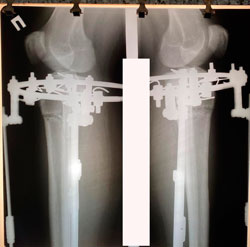

на фиксации

image-17-09-20-05-23-1.jpg

image-17-09-20-05-23.jpg